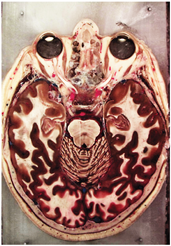

Table 2, Table 3, Table 4 and Table 5 present the results obtained through the multi-objective optimization image enhancement approach. Specifically, Table 2 and Table 3 show the results for natural images, while Table 4 and Table 5 display medical images. The tables are organized as follows: the first and second columns list the image names and their corresponding original, unenhanced versions. The third to fifth columns showcase the selected points from the Pareto front, representing the maximum contrast, knee point, and maximum detail, in that order. The final column illustrates the obtained Pareto front through the optimization process, with red, green, and orange points indicating the images that achieved maximum contrast, knee point, and maximum detail, respectively.

Table 4.

Medical image results—1.

For medical images, there are instances where differences are more perceptible. For example, in the Medical3 image, the maximum contrast solution makes it difficult to visualize the internal details of the basophil (a white blood cell highlighted in the box), which could result in a less accurate interpretation. In contrast, the knee and maximum detail solutions provide a clearer view of the interior of the white blood cell. Similarly, in the Medical5 image, the maximum contrast solution highlights the hand and arm bone structures. However, the maximum detail image offers a more precise view of the internal structures within the bones (see the highlighted region), which is crucial for a more detailed evaluation. Another notable example is the Medical8 image, where the maximum detail solution offers a more detailed view of the internal structure of the eosinophil (another type of white blood cell). However, the maximum contrast image improves the visibility of red blood cells. As shown in the yellow box, this solution reveals a red blood cell that is nearly imperceptible in the other solutions. An interesting case is the Medical6 image, where only a few non-dominated solutions are present on the Pareto front. Despite the similarities among the preferred solutions, the nodules are much more perceptible in the enhanced images than in the original image, as observed in the highlighted region.